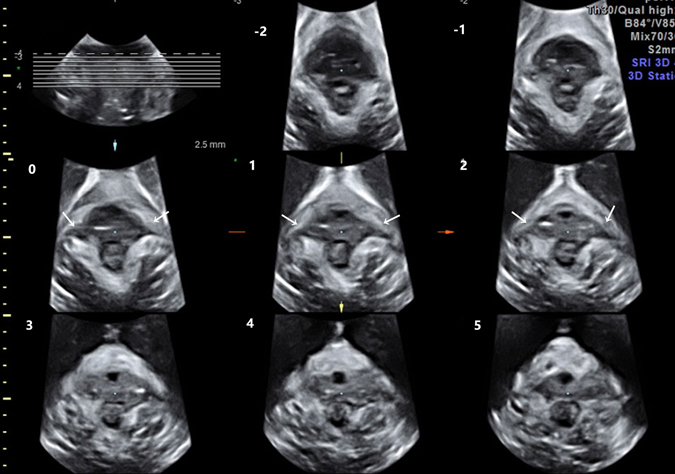

Figure 2.

The transperineal views of the puborectalis muscle obtained by TUI show bilateral avulsion, as marked by arrows. There are abnormal echo inserted between the muscle and pelvic sidewall on slice −1 to slice.

No cases of puborectalis avulsion were found in the nulliparae group. The levator hiatus had a compact structure outlined by the pubis and puborectalis. The puborectalis was continuous and formed a V-shaped sling running from the pelvic sidewall towards the anorectal junction. The puborectalis closely attached to the interior edge of the inner surface of the pubic bone (without abnormal echo inserted) and surrounded the posterior rectum on the dorsal side (Fig. 1). Puborectalis avulsion was identified as a loss of continuity between the muscle and the pelvic sidewall, with no muscle remaining on slices 0, 1, and 2 of TUI (Fig. 2). The iliococcygeus is difficult to observe on translabial ultrasound images. In the 80 vaginally parous women, puborectalis avulsion was diagnosed in 11 women (13.75%). Defects were on the left (n = 3), on the right (n = 4) or bilateral (n = 4). Of these 11 cases of puborectalis avulsion, 7 were spontaneous vaginal deliveries, and 4 were forceps-aided vaginal deliveries. Puborectalis avulsion was more common in forceps-aided vaginal delivery than in spontaneous vaginal delivery (χ2 = 12.703, P < 0.001). Furthermore, in the primiparae group, the LUG in women with puborectalis avulsion were much larger than that of women with an intact levator (P < 0.001) (Table 2).